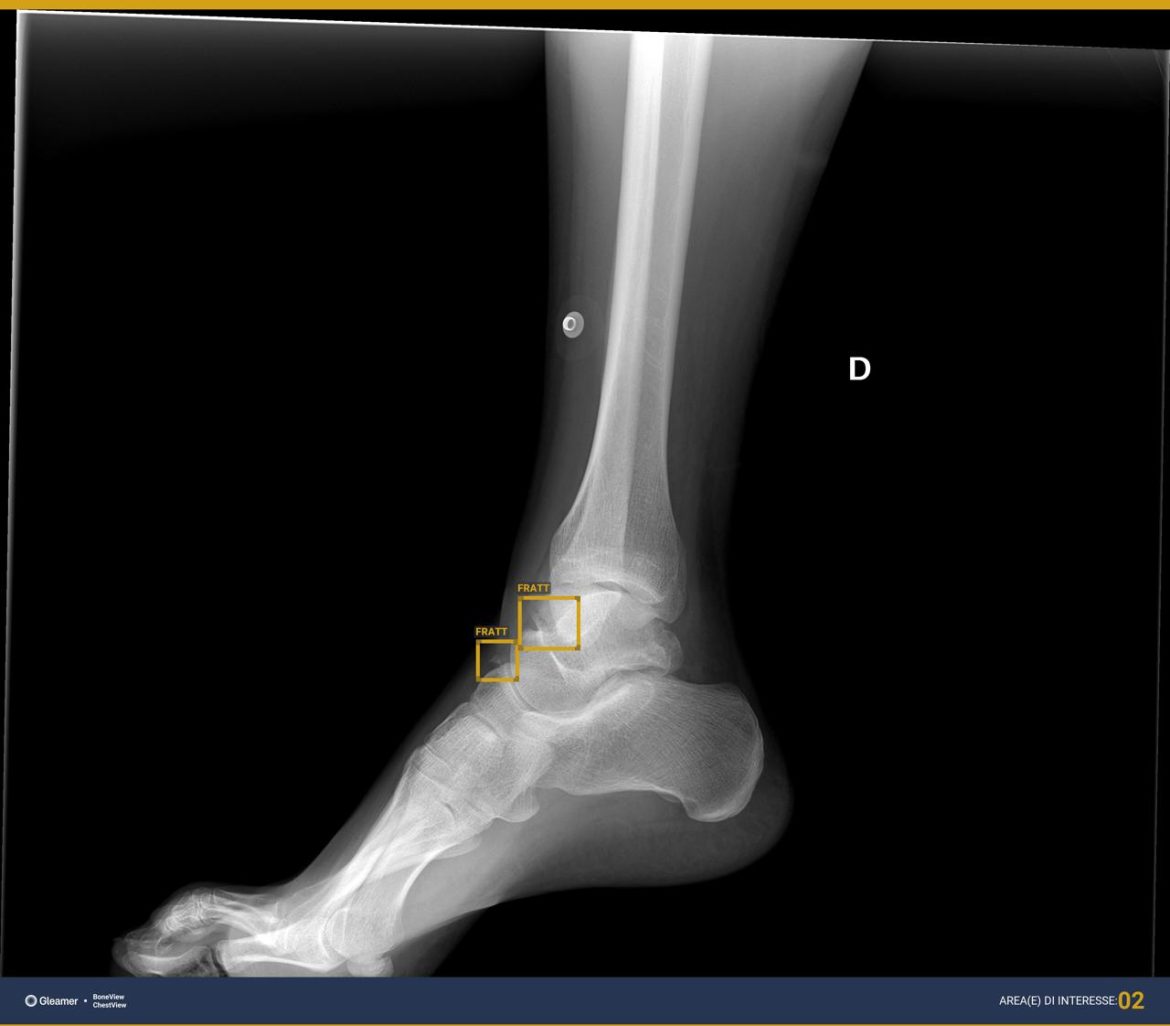

Milano, 2 ago. (Adnkronos Salute) – All’ospedale San Camillo di Roma le radiografie le rivede l’intelligenza artificiale. Un assistente virtuale che ‘ci butta un occhio’ per fornire un second look, una seconda lettura, in tempo reale. La Radiologia di urgenza/emergenza dell’azienda ospedaliera capitolina – informa l’Ao – da circa 6 mesi ha sperimentato l’implementazione di software di Ai nell’ambito della radiodiagnostica, capaci di offrire supporto alla diagnosi per lesioni osteoarticolari e patologie polmonari.La Uosd Radiologia di emergenza/urgenza del San Camillo, diretta da Michele Galluzzo e afferente al Dipartimento Emergenza Accettazione e delle Chirurgie specialistiche guidato da Pierluigi Marini – spiega una nota – gestisce flussi di lavoro estremamente intensi, sia dal punto di vista del numero di pazienti che della complessità degli esami. E’ attiva h24 per 365 giorni l’anno ed effettua un numero totale annuo di prestazioni pari a 84.561, di cui 41.792 esami Tc e 35.084 esami radiografici. Questo richiede particolare attenzione nella refertazione, anche nei momenti più sfavorevoli, come ad esempio di notte. A partire da fine 2023, dunque, un team composto da Galluzzo, da Riccardo Ferrari, dirigente medico della Radiologia di emergenza/urgenza e presidente eletto della sezione di Informatica e Ai della Sirm (Società italiana di radiologia medica ed interventistica), e da Annarita Caporaso, direttore dell’Ingegneria clinica, ha avviato gli studi di fattibilità per implementare la dotazione tecnologica della Radiologia d’urgenza con software alimentati dell’intelligenza artificiale, con l’obiettivo di “ottimizzare e migliorare, grazie alle nuove tecnologie, esiti, tempi e utilizzo delle risorse”. E’ stato quindi acquisito un software che lavora come ‘secondo lettore’ delle immagini radiografiche, in grado di individuare lesioni osteotraumatiche quali fratture, lussazioni e versamenti, oltre a lesioni focali dell’osso, e di fornire informazioni di supporto al radiologo nel diagnosticare alcune patologie polmonari in condizioni di urgenza, anche in radiogrammi eseguiti in situazioni difficili, per esempio in pazienti allettati. “L’intelligenza artificiale è una tecnologia con un forte impatto nella diagnostica per immagini – afferma Galluzzo – In condizioni di urgenza è un utile supporto diagnostico per il medico radiologo. Importante sottolineare – precisa – che la tecnologia non sostituisce il medico, ma rappresenta un valido strumento nell’ottica del miglioramento delle performance diagnostiche e gestionali”.”In un ambito fortemente tecnologizzato come la radiodiagnostica – aggiunge Ferrari – l’implementazione di tecnologie basate su intelligenza artificiale permette al medico radiologo di utilizzare automazioni e supporto alla diagnosi per poter correttamente interpretare le immagini e diagnosticare le patologie. L’utilizzo di tecnologie di supporto alla diagnosi nella radiologia d’urgenza, e in un reparto ad alta intensità di afflusso come il nostro, vuol dire fornire a colleghi e pazienti le tecnologie più all’avanguardia per la diagnosi e la cura”. E’ stato necessario un training specifico del personale medico e tecnico – si evidenzia nella nota – con precise istruzioni sui vantaggi e sui limiti dell’uso di queste tecnologie. “Riteniamo che il sistema acquisito abbia un ottimo rapporto qualità prezzo – rimarca Caporaso – aspetto anche quest’ultimo rilevante in un’ottica di garanzia della qualità delle prestazioni erogate nel rispetto comunque del contenimento della spesa sanitaria. Siamo pronti ad acquisire altri software basati sull’Ai che permettano di supportare il radiologo anche in patologie tempo dipendenti, con una prelettura e segnalazione prioritaria dei reperti di particolare interesse e urgenza”. Un progetto che si incardina in quello più ampio fortemente voluto dalla direzione strategica – si legge – di portare l’azienda ospedaliera San Camillo-Forlanini a essere prima tra le Ao laziali nell’utilizzo di tecnologie basate su intelligenza artificiale.